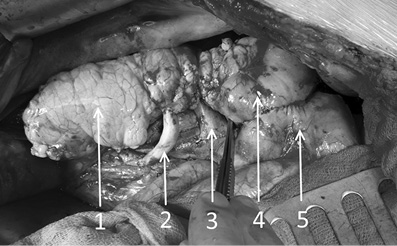

Результаты. После реперфузии мы визуализировали интенсивное и равномерное кровенаполнение всех отделов органов, включая культю донорской двенадцатиперстной кишки (рис. 2).

Рис. 2. Интраоперационная фотография трансплантата поджелудочной железы с изолированным кровоснабжением по селезёночной артерии: 1 — трансплантат поджелудочной железы; 2 — a. lienalis; 3 — v. porta; 4 — культя duodenum донора; 5 — duodenum реципиента